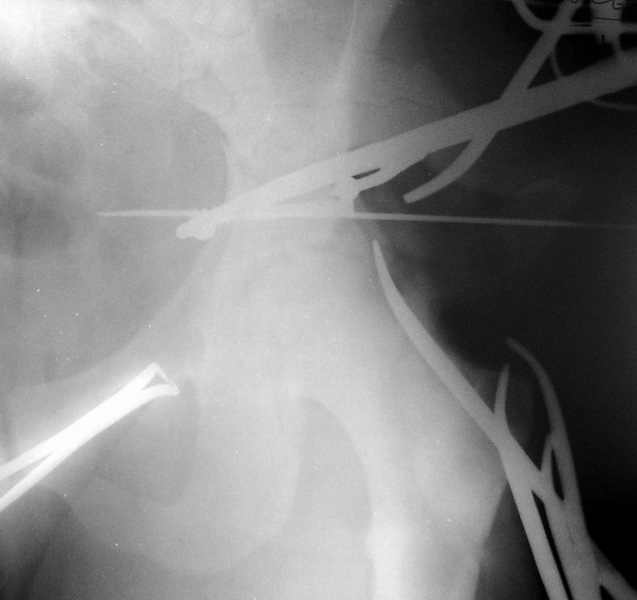

Сегодня на приеме был пациент, чьи начальный снимок напомнил обсуждаемый сейчас (см. выше). Снимки в других проекциях, показывающие истинный характер повреждения, ниже. Это inlet проекция (вход в таз) и запирательная проекция Judet.